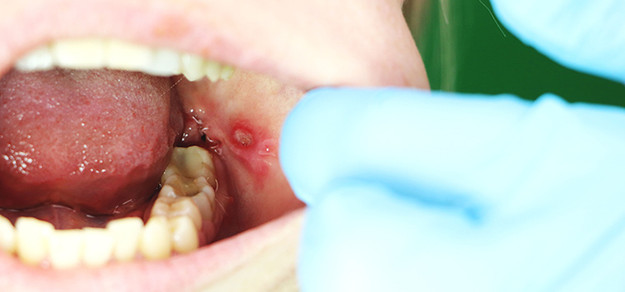

Namaste everyone 🙏 Manav Yog Wellness Center offers a unique approach to treating mouth ulcers through the use of Electro Homeopathy medicine. Our specialized treatment focuses on leveraging the principles of Electro Homeopathy to address and alleviate the discomfort caused by mouth ulcers. Our experienced practitioners at Manav Yog Wellness Center are dedicated to providing personalized care, aiming to restore balance and promote overall oral health. Discover a holistic solution that combines traditional wisdom with modern techniques to effectively manage and cure mouth ulcers at our wellness center. Mouth Ulcer treatment at Manav Yog Wellness Center |Mouth ulcer treatment by Electro Homeopathy | Mouth Ulcer treatment near me | Electro Homeopathy treatment in Bangalore | |Manav Yog Wellness Center |Ayurvedic healing|Electro Homeopathy treatments|Yoga for health|Disease management through yoga|Holistic wellness programs|Natural healing practices|Ayurvedic remedies|Electro Homeopathy solutions|Yoga therapy sessions|Traditional medicine center|Ayurvedic lifestyle|Energy healing techniques|Mind-body balance|Yoga for chronic diseases|Herbal remedies for health|Integrative medicine approaches| Electro Homeopathy benefits|Meditation for healing| Wellness retreat programs|Ayurvedic consultations| Yoga for mental health|Disease prevention through Ayurveda|Electro Homeopathy remedies list| Ayurvedic nutrition|Yoga for specific ailments|Alternative medicine center|Energy balancing practices|Ayurvedic herbs and spices| Electro Homeopathy research|Yoga for immune system support|Ayurvedic principles|Holistic healing center|Electro Homeopathy case studies| Yoga for stress relief|Disease control through Ayurveda|Mindfulness practices|Ayurvedic lifestyle management|Electro Homeopathy practitioners| Yoga for respiratory health|Herbal supplements for wellness|Ayurvedic detox programs|Electro Homeopathy testimonials|Yoga for cardiovascular health|Integrative wellness approach|Ayurvedic massage therapies|Energy medicine techniques| Ayurvedic yoga practices|Electro Homeopathy and Ayurveda combination|Yoga for digestive disorders| Disease reversal through Ayurveda|Holistic health and wellness|Electro Homeopathy treatment plans| Ayurvedic skincare solutions|Yoga for joint health| Ayurvedic lifestyle tips|Energy healing modalities| Disease management with natural remedies| Electro Homeopathy and yoga synergy| Meditation for holistic health|Ayurvedic remedies for common ailments|Yoga for hormonal balance| Integrative health programs|Electro Homeopathy and chronic conditions|Ayurvedic practices for vitality| Mind-body medicine techniques|Disease prevention strategies|Yoga for pain management| Herbal formulations in Electro Homeopathy| Ayurvedic approaches to specific diseases| Holistic healing philosophies|Electro Homeopathy wellness center|Yoga for mental clarity| Ayurvedic approaches to inflammation|Disease control through natural remedies|Energy balancing yoga practices|Ayurvedic herbs for overall health| Electro Homeopathy and immune system support| Wellness retreats with yoga and Ayurveda| Mindfulness in disease management|Yoga for holistic well-being|Ayurvedic dietary recommendations| Electro Homeopathy and holistic health| Ayurvedic solutions for stress|Integrative wellness retreats|Disease-specific Ayurvedic treatments| Yoga for energy flow|Electro Homeopathy and lifestyle modifications|Ayurvedic approaches to mental disorders|Holistic medicine center|Energy healing for disease prevention|Yoga for spiritual well-being| Ayurvedic practices for longevity|Electro Homeopathy and traditional healing| Disease management through energy medicine| Ayurvedic detoxification protocols| Yoga for overall vitality|Integrative health and wellness center|Electro Homeopathy and emotional well-being| Ayurvedic wisdom for a healthy life|